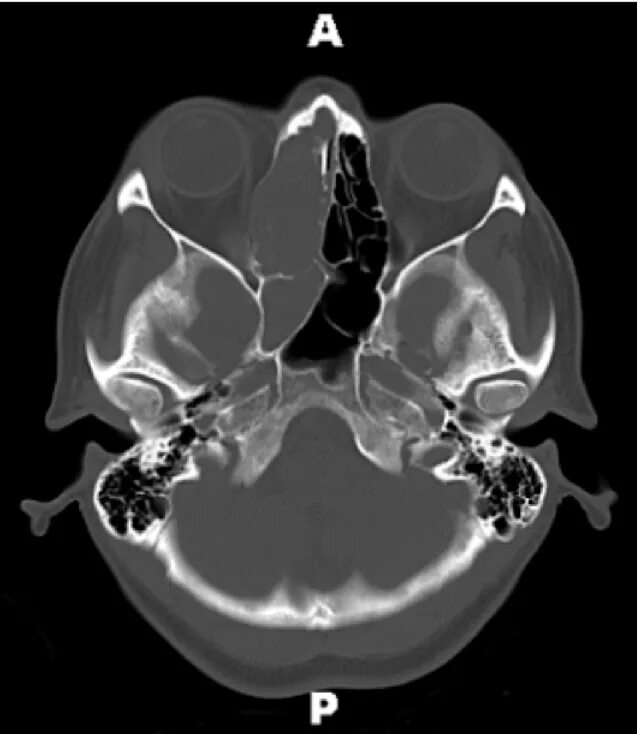

Синусит на кт